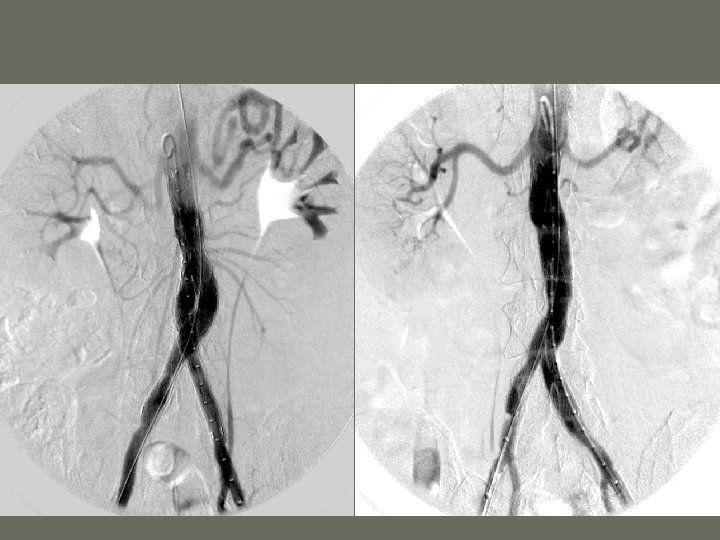

Interventional Procedures 3. Percutaneous Transluminal Angioplasty – PTA • purpose is to _____ a stenotic vessel or to cannulize short arterial occlusions • compresses the _______ material against the vessel wall • arterial pressures are recorded prior to procedure

Interventional Procedures • Uses a ______ catheter – catheter placed over the stenosis and inflated with contrast medium

Interventional Procedures 4. Stent placement • Cage-like metal or plastic device placed in a vessel to enlarge the lumen • acts as ______ for the vessel wall • indicated when balloon angioplasty is _________